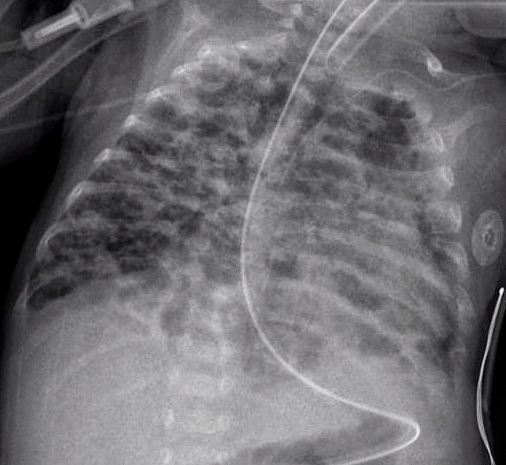

출생 시 체중이 900g, 재태기간 27주였던 미숙아는 생후 30일 동안 인공호흡기를 통한 호흡 지원을 받아왔다. 이 아기는 생후 초기에 동맥관 개존증으로 인도메타신 치료를 받았으며, 생후 5주에 괴사성장염으로 인해 수술을 받았다. 현재 생후 10주가 되었으나 여전히 인공호흡기 없이는 호흡이 어렵고, 산소 공급을 중단하면 심한 청색증이 발생한다. 아래는 아기의 가슴 X선 사진 결과이다. 이 아기에게 가장 적절한 치료 방법은 무엇인가?

2) CXR: 기포성 폐(bubbly lung), 폐사이질 혼탁 등 다양